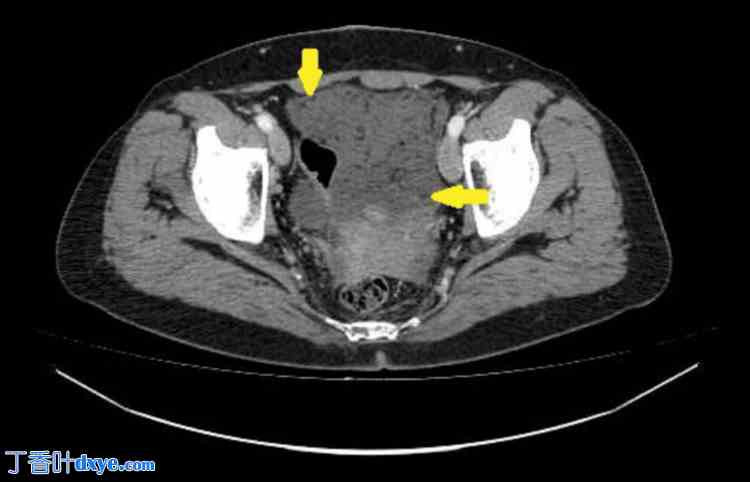

胸部、腹部和盆腔CT扫描(静脉注射造影剂)显示肝周、脾周及盆腔内多处低密度积液(提示为粘蛋白)。在大网膜、小网膜及侧沟内发现聚集性腹膜沉积物,提示腹膜广泛受累。胸部和腹部器官未见其他病理改变。扫描区域淋巴结未肿大。未见骨质破坏或成骨细胞活动征象(图1-4)。

图4. 腹膜转移灶及腹部和盆腔局部积液的CT成像。

冠状面多平面重建。箭头所示为大网膜转移灶。